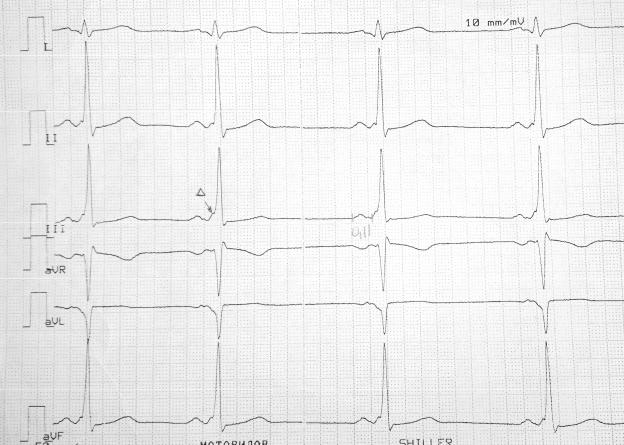

Рис. 9. AV-блокада I степени.

1. Интервал P-Q стабильно >200мс – AV-блокада I степени